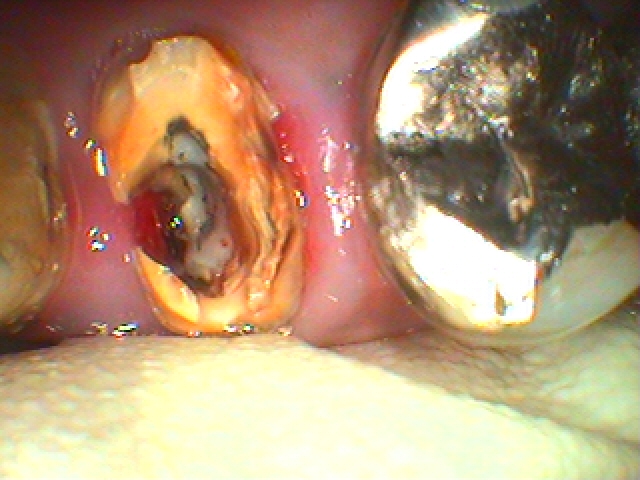

右上の4番目の歯の歯茎が最近になって腫れて痛みだした診てほしい|お知らせ |広島市安佐南区の歯科医院 右上の4番目の歯の歯茎が最近になって腫れて痛みだした診てほしい トップ お知らせ・ブログ お知らせ 右上の4番目の歯の歯茎が最近になって腫れて痛みだした診てほしい 右上の4番目の歯の歯茎が最近になって腫れて痛みだした診てほしい 問題の歯になります 近心部の歯茎が腫れています 被せがしてあります かぶせを外していきました 土台を外すと中に穴が開いています これが原因で腫れてきていました 抜歯即時インプラント埋入を行っていきます 補填材を入れて終了となります セラミックにて修復しています このように抜歯即時インプラント埋入を行っています きれいに仕上がっています Web診療予約 初めての方へ 選ばれ続ける理由 院内設備について 歯が痛いしみる一般歯科 歯がぐらぐらする歯周病 健康な歯を保ちたい予防歯科 子供の虫歯予防をしたい小児歯科 銀歯をセラミックに審美歯科 白い歯を目指しませんか?ホワイトニング 矯正専門医がいるので安心矯正歯科 抜けた歯を補いたいインプラント・入れ歯 医院案内 スタッフ紹介 メリィハウス歯科クリニックオフィシャルホームページ ラベンダー歯科クリニックオフィシャルホームページ お知らせ・ブログ ホーム 診療科目 一般歯科 歯周病治療 予防治療 小児歯科 審美治療 ホワイトニング 矯正歯科 入れ歯・インプラント マウスピース矯正 初めての方へ 院長・スタッフ 設備紹介 医院案内・アクセス メニューを閉じる